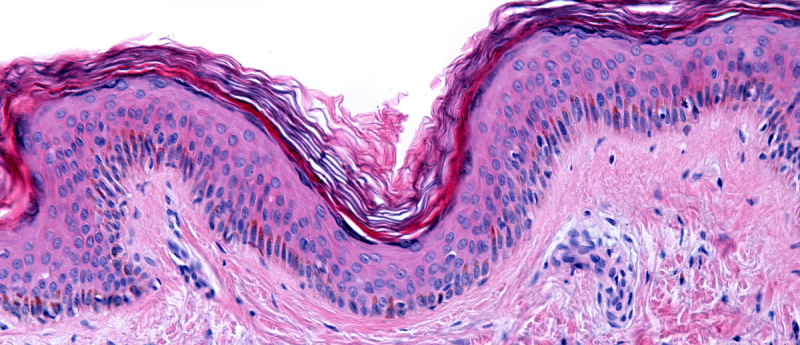

In this White Paper, MatTek, now part of Sartorius, details a highly differentiated 3D small-intestine tissue model that uses primary human stem cells to provide a more accurate alternative to animal testing and traditional cell models for drug discovery and toxicity screening.

Discover how this human-relevant model enables pharmaceutical companies to assess drug metabolism, absorption, efficacy, and gastrointestinal toxicity more cost-effectively and earlier in the pre-clinical development process.